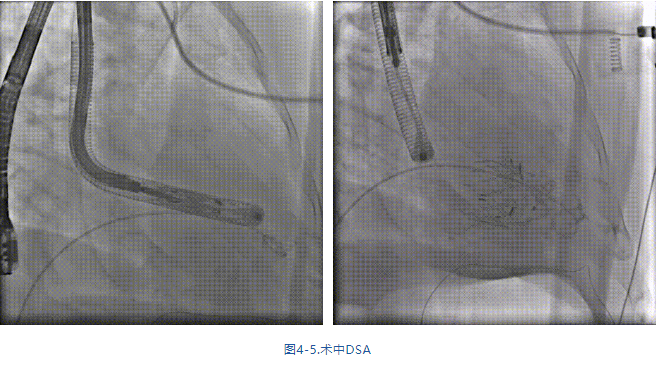

手術(shù)在全麻狀態(tài)下進行,采用經(jīng)右側(cè)頸靜脈入路,在TEE和DSA的指引下緩慢送入輸送器進入體內(nèi),進入右室后釋放室間隔錨定裝置,旋轉(zhuǎn)輸送器,使得錨定裝置對準室間隔面;釋放前瓣夾持件,確定夾持件位于右室側(cè)后釋放人工瓣膜盤片,DSA及超聲確認盤片位于右房側(cè),并適時調(diào)整瓣膜的同軸性。在DSA和超聲的監(jiān)視下調(diào)整室間隔錨定件貼合室間隔,釋放室間隔錨定裝置。再次確認瓣膜的穩(wěn)定性和同軸性后,將輸送器撤出體內(nèi),最終完成瓣膜植入(圖4-5),手術(shù)室即刻拔除氣管插管。術(shù)后超聲提示人工三尖瓣同軸性良好,瓣架固定牢靠,無反流和瓣周漏,術(shù)后三尖瓣平均跨瓣壓差顯著降低。